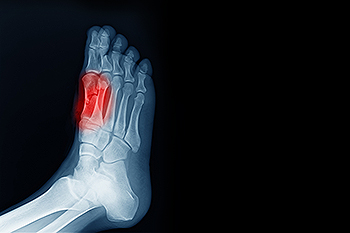

Their diagnostic tools—ranging from gait analysis to imaging—allow early detection of subtle abnormalities that, left unaddressed, can escalate into debilitating long-term issues.

The human foot is a marvel of biological engineering, consisting of 26 bones, 33 joints, and over 100 muscles and ligaments working in synchrony. Podiatrists leverage deep anatomical insight to identify how misalignment, wear patterns, or systemic diseases disrupt this balance.